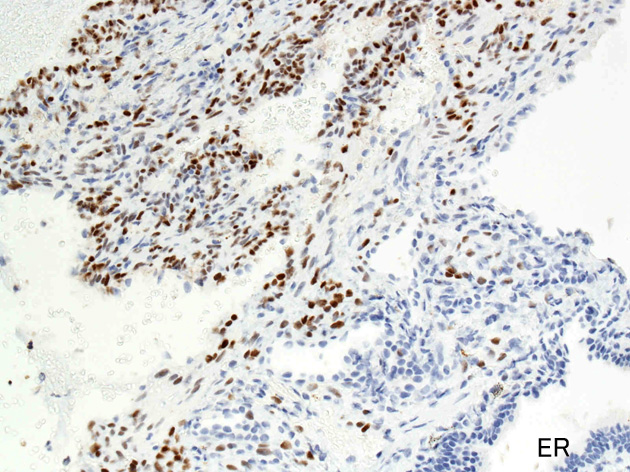

免疫染色

ER.jpg

Estrogen receptorProgesteron receptor